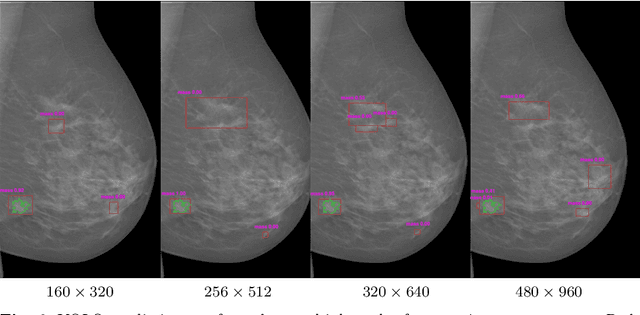

Abstract:Mammography is the primary imaging modality used for early detection and diagnosis of breast cancer. Mammography analysis mainly refers to the extraction of regions of interest around tumors, followed by a segmentation step, which is essential to further classification of benign or malignant tumors. Breast masses are the most important findings among breast abnormalities. However, manual delineation of masses from native mammogram is a time consuming and error-prone task. An integrated computer-aided diagnosis system to assist radiologists in automatically detecting and segmenting breast masses is therefore in urgent need. We propose a fully-automated approach that guides accurate mass segmentation from full mammograms at high resolution through a detection stage. First, mass detection is performed by an efficient deep learning approach, You-Only-Look-Once, extended by integrating multi-scale predictions to improve automatic candidate selection. Second, a convolutional encoder-decoder network using nested and dense skip connections is employed to fine-delineate candidate masses. Unlike most previous studies based on segmentation from regions, our framework handles mass segmentation from native full mammograms without user intervention. Trained on INbreast and DDSM-CBIS public datasets, the pipeline achieves an overall average Dice of 80.44% on high-resolution INbreast test images, outperforming state-of-the-art methods. Our system shows promising accuracy as an automatic full-image mass segmentation system. The comprehensive evaluation provided for both detection and segmentation stages reveals strong robustness to the diversity of size, shape and appearance of breast masses, towards better computer-aided diagnosis.